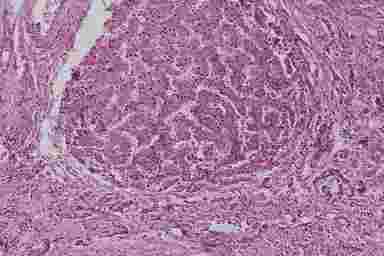

Алкогольный гепатит. При развернутой картине острого алкогольного гепатита гепатоциты находятся в состоянии баллонной и жировой дистрофии; практически обязательное присутствие последней послужило поводом для введения термина “алкогольный стеатогепатит” (рис. 6.2).

Алкогольная болезнь печени

Рис. 6.2. Алкогольная болезнь печени (биоптат печени, окраска г/э, х200). Алкогольный гепатит на фоне диффузного крупнокапельного ожирения гепатоцитов. Фиброз

В цитоплазме гепатоцитов выявляется алкогольный гиалин (тельца Мэллори), который представляет собой эозинофильные включения, состоящие из конденсированных промежуточных микрофиламентов цитоскелета. Тельца Мэллори характерны для алкогольного поражения печени, однако, также могут встречаться при ПБЦ, болезни Вильсона-Коновалова, раке печени и т.д.

Имеется в той или иной степени выраженный перивенулярный и перисинусоидальный фиброз преимущественно вокруг центральных вен, очаговая инфильтрация долек нейтрофилами с некрозом гепатоцитов в зоне инфильтрации. В различной степени выраженные фиброзные изменения и воспалительная клеточная инфильтрация наблюдаются также в портальных трактах.